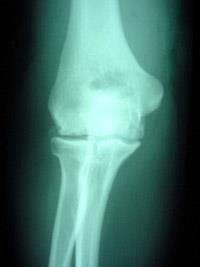

No Bones About It Osteosarcoma Is A Bad Bone Cancer Creature Comfort Care Llc from images.squarespace-cdn.com Trouble is, bone cancer symptoms can mimic those of other, more common conditions, including arthritis, fractures and other acute skeletal injuries, and benign bone tumors. Or a small lump on the leg that becomes tender to the touch. Arthritis and cancer are two processes that can lead to severe, unremitting pain that worsens over time. It is important to remember that dogs and cats are stoic and particularly good at hiding their pain. Bone broths contain essential minerals in forms that your pet's body can easily absorb. Identifying whether your aches and pains are indicative of a nonmalignant skeletal condition or symptoms of bone cancer may potentially mean the difference between life and. Surprisingly, joint issues are common in dogs of all breeds and ages. Chondrosarcoma is a malignant form of bone cancer in dogs characterized by a tumor of neoplastic chondroid and fibrillar matrix forming in cartilage.

In addition to diet, supplements, and medications, there are also therapy treatment options available to help manage a dog's arthritis pain. Physical therapy, like appropriate forms of regular. In 1969, a study came out that reported the incidence of mammary cancer related to the timing of spay. A degenerative disease, arthritis most often results from everyday wear and tear on the joints. Does your dog suffer from joint problems? While i have the ability to improve my patient. Radiation therapy may also be an option. According to the arthritis foundation, one in five (or 20 percent) of dogs can experience arthritis. Chondrosarcoma is a malignant form of bone cancer in dogs characterized by a tumor of neoplastic chondroid and fibrillar matrix forming in cartilage. Bone tumors are more frequent in larger dog breeds, but may occur in medium sized or smaller dogs also. Identifying whether your aches and pains are indicative of a nonmalignant skeletal condition or symptoms of bone cancer may potentially mean the difference between life and. Lameness or a distinct swelling may be noted. Or a small lump on the leg that becomes tender to the touch.

They can include swelling, lameness, and joint or bone pain.